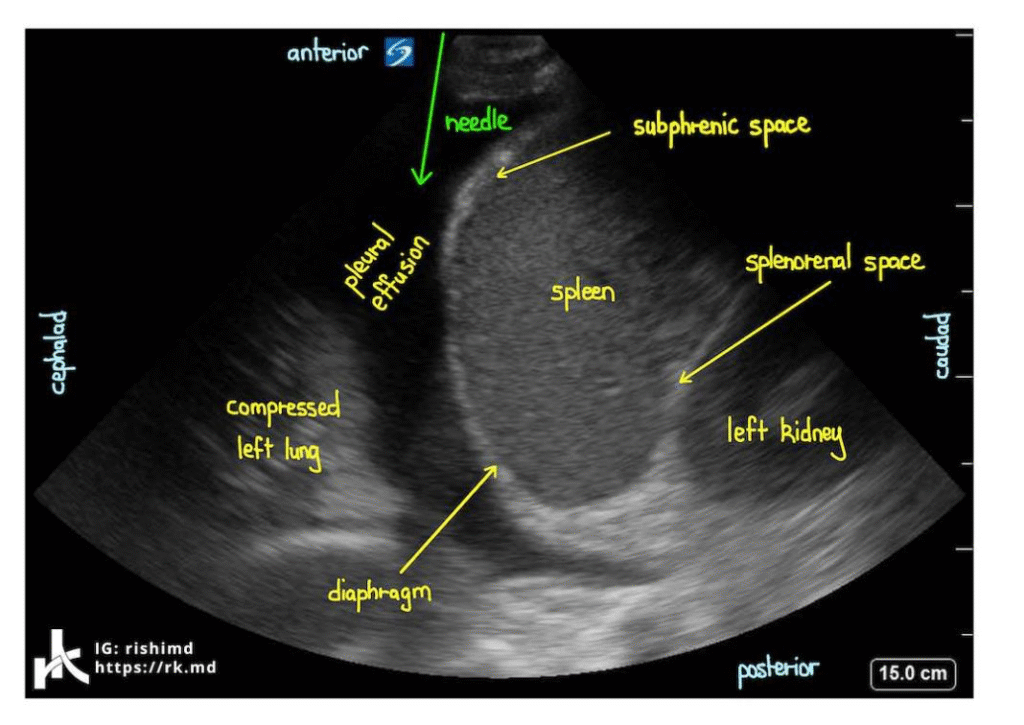

- Sono Thorax: Goldstandard für Nachweis + Punktion

Pleura-Punktion

- Indikation: Diagnostik, Symptomlinderung

- Lagerung: Sitzend, Arme aufgestützt

- Stichstelle: Hintere Axillarlinie, oberhalb der Rippe (Gefäß-Nerven-Bündel läuft unterhalb!)

- Material: Steril, Lokalanästhesie, 20–50 ml für Diagnostik

- Komplikationen: Pneumothorax, Nachblutung, Infektion, Reexpansionsödem

- Sono vor Punktion = Goldstandard